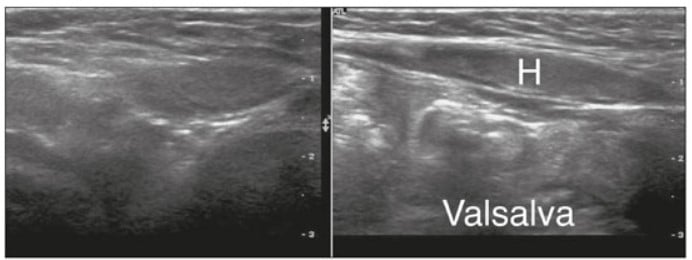

Hérnia inguinal e femoral

A hérnia inguinal ocorre quando conteúdo intra-abdominal protrui pelo canal inguinal. Quando encarcerada, pode causar obstrução intestinal; na estrangulação, há risco de necrose.

No caso das hérnias femorais, teremos uma protrusão de conteúdo abdominal através de um defeito da parede abdominal. Ela comumente encardera e estrangula, nesses casos, o paciente pode apresentar uma massa irreversível na região inguinal ou escrotal, dor intensa e sintomas obstrutivos (vômitos, distensão abdominal). Nesse contexto, o usg com doppler, há presença de alças intestinais ou epíplon no saco herniário, com ou sem vascularização.

Outros achados ultrassonográficos possíveis são:

- Conteúdo intestinal ou gorduroso no canal inguinal.

- Movimentação dinâmica com manobra de Valsalva.